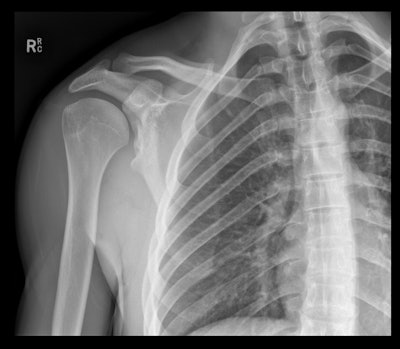

Dysplastic glenoid tubercle predisposing patient to recurrent dislocations.All figures courtesy of Dr. Graeme Abreu, Royal Brisbane and Women’s Hospital, and presented at RANZCR 2025 ASM.

Greater tuberosity fracture overlooked on initial imaging.

Acromioclavicular dislocation in suspected shoulder dislocation.